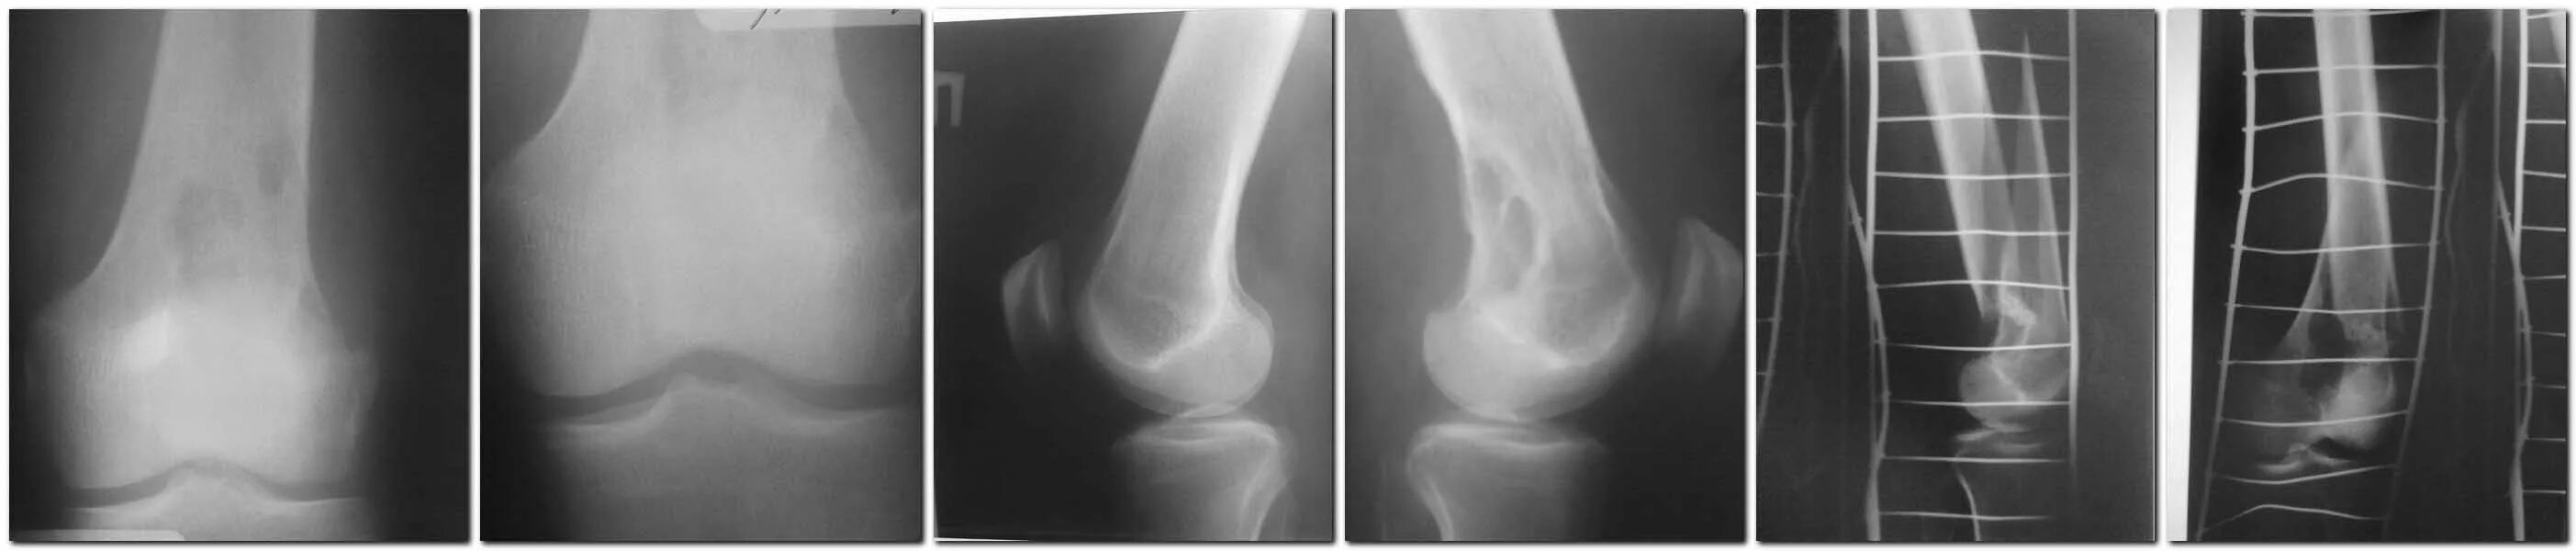

Патологический перелом бедра